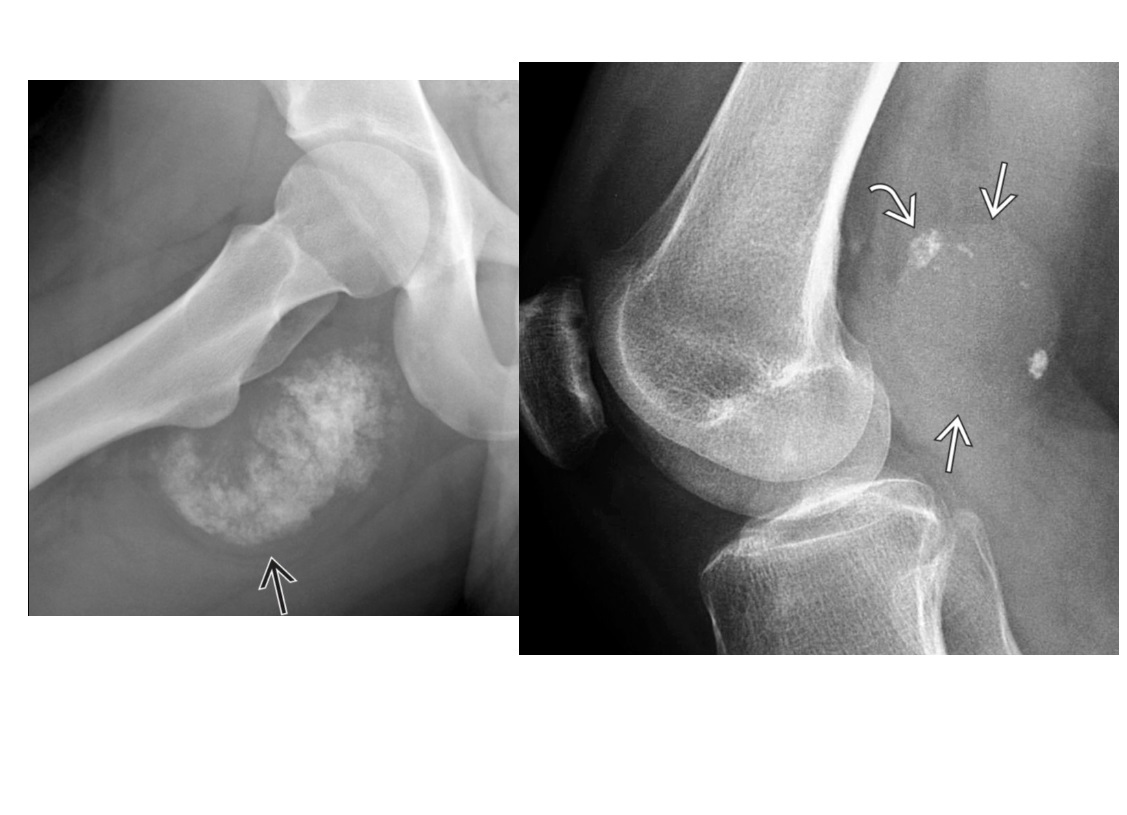

Segond fracture

Lateral tibial plateau

Associated with ACL tear (75%) and internal rotation

MR SL = Medial Reverse Lateral Segond

Reverse Segond fracture

Medial tibial plateau

Associated with PCL tear with external rotation. Associated with medial meniscus injury.

Arcuate sign

Avulsion of the proximal fibula

Associated with PCL tear